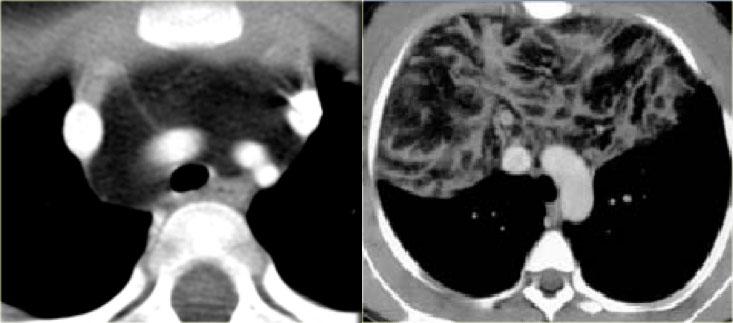

Phim ngực cho thấy các đặc điểm điển hình của u lympho Hodgkin, ví dụ: một khối trung thất trước.

Các hình ảnh CT của cùng bệnh nhân cho thấy một khối mô mềm lớn ở trung thất trước, xuất phát từ tuyến ức.

Có hạch cạnh khí quản kèm theo (mũi tên).

Hai trường hợp u lympho Hodgkin khác.

Các trường hợp này cũng cho thấy khối trung thất trước và hạch cạnh khí quản to.